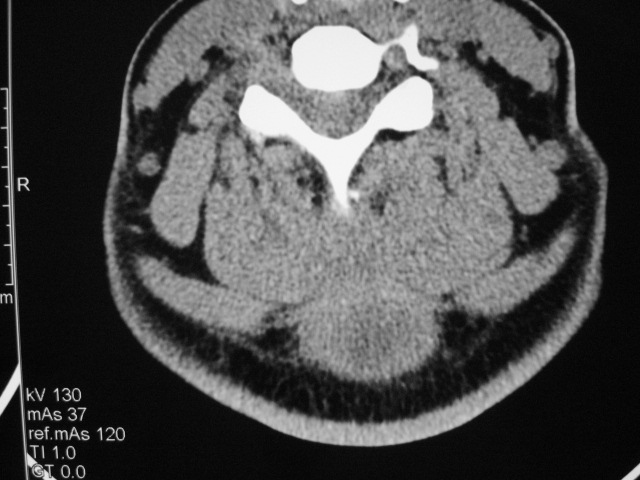

女,46岁,发现颈后区肿块3月余.

颈后软组织肿块,内可见坏死区及点状钙化,邻近颈椎棘突可见破坏,邻近肌间隙模糊,肿块周围脂肪间隙可见索条状影。

考虑:1)感染,结核可能;

2)肿瘤不能排除。